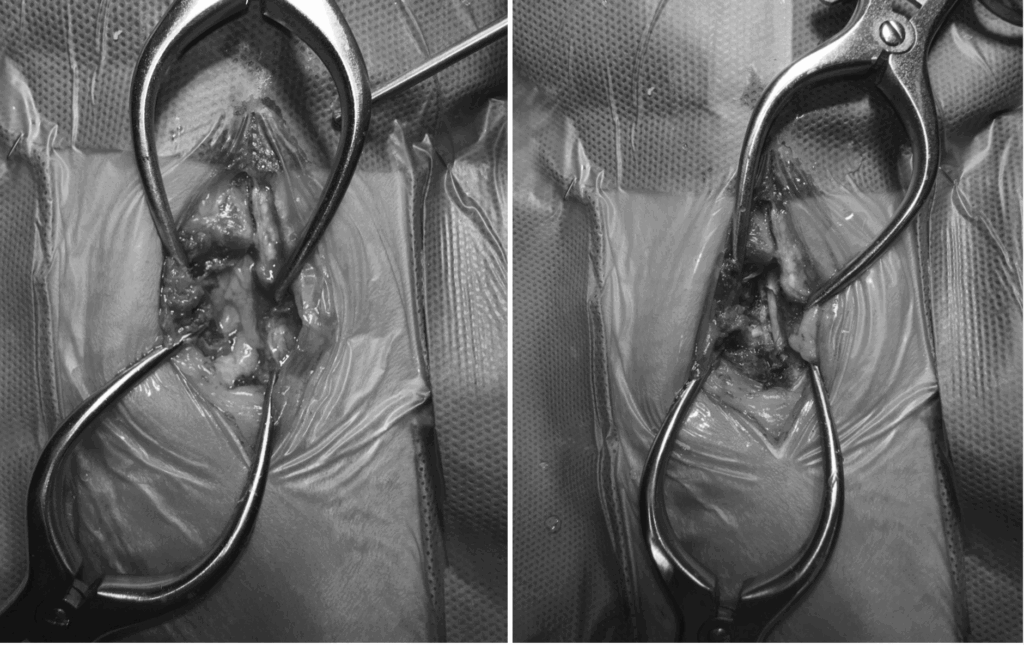

수술 과정

환자는 즉시 수술적 치료를 결정하였고, 흉추 12-13 Hemi-laminectomy(반쪽 추궁 절제술)를 진행했습니다.

우선 추궁을 절개하여 병변 부위에 접근한 후, 돌출된 추간판 물질을 제거하고, 정상적인 척수 실질이 보일 때까지 수술 부위를 점차 넓혀주며 압박을 해소했습니다.

강아지 디스크 수술 / 출처: 24시온숲동물의료센터

강아지 디스크 수술 / 온숲동물의료센터

이 과정은 단순히 추간판만 제거하는 수준이 아니라, 광범위하게 척수를 감압해야 하는 고난도 수술로 진행되었습니다.